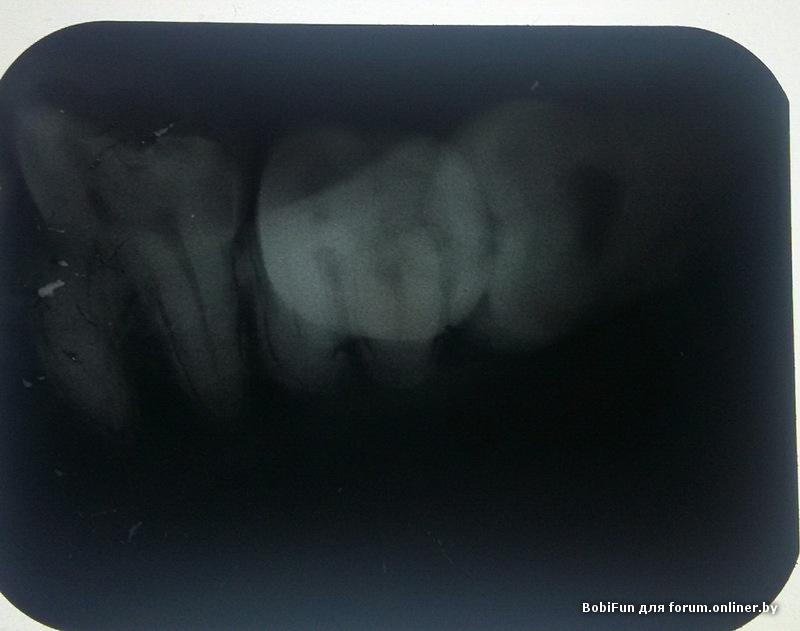

сделала вчера снимок "лежачей" восьмерки нижней справа

снимок сделан был в городской поликлинике, а это снимок год назад ,сделанный в частной клинике

А это четверка после удаления нерва(прошел год), в ней дискомфорт,если чем-то постучать то неприятно

. По снимку мне кажется с ней все нормально,но отчего же тогда дискомфорт может возникать?

перепломбировать.

BobiFun:

Подскажите пожалуйста,насколько все плохо с зубом?он беспокоит редко. и куда лучше обратиться с моим случаем?я так понимаю придется его доставать через разрез десны....

А что восьмерке - ей ничего. Просто когда она убъет 7ку, тогда будет поздно, но удалять будет сразу два легче)) :D